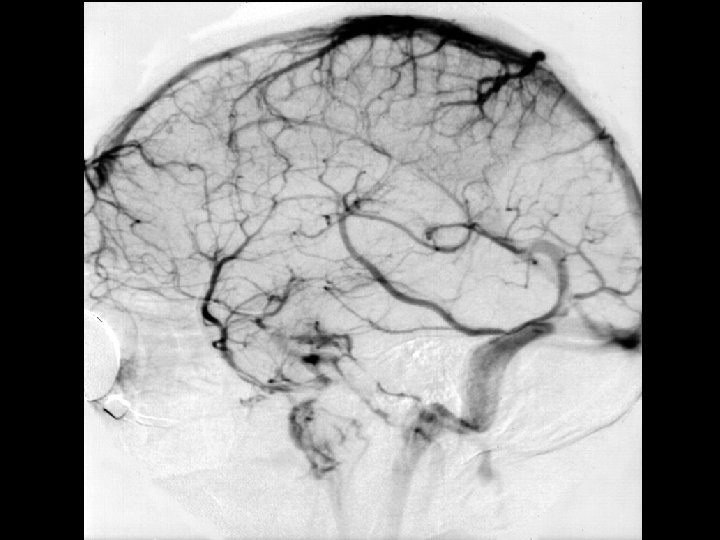

Angiographic digression to aid the understanding of venous angiography Michigan Neurosurgery

Scout view Michigan Neurosurgery

Arterial phase Michigan Neurosurgery

Capillary phase Michigan Neurosurgery

Early Venous phase Michigan Neurosurgery

Late Venous phase Michigan Neurosurgery